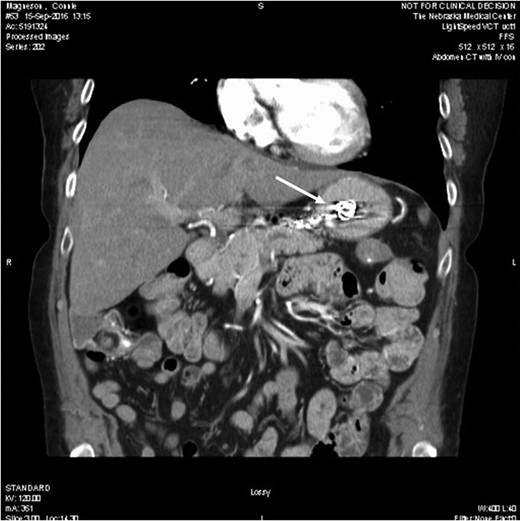

A 65 -year-old woman with a known history of multiple splenic and hepatic aneurysms was admitted to our hospital in October 2012 with acute abdomen. Abdominal computed tomography angiography showed rupture of splenic aneurysm with active extravasation of contrast and associated large left upper quadrant hematoma with small hemoperitoneum (Fig. 1). Visceral angiogram confirmed the presence of three fusiform aneurysms involving midsplenic artery (Fig. 2). The distal most aneurysm demonstrated large extravasation (Fig. 3). Coil embolization of the proximal and midsplenic artery aneurysm was performed using multiple Nester coils (Cook Medical, USA) with cessation of antegrade flow (Fig. 4). Attempt to access distal portion of the splenic artery was unsuccessful. She recovered well and was discharged 4 days later. In December 2016, she was admitted with dyspepsia and severe iron deficiency anemia requiring blood transfusion. A colonoscopy and upper endoscopy were performed which showed the presence of metallic coils in the stomach (Fig. 5). The patient subsequently underwent a combined upper endoscopy and laparoscopy. Three 5 mm ports were used to expose the lesser sac in event of hemorrhage during extraction of the coil endoscopically. An atraumatic bowel clamp was placed distal to the Treitz ligament to prevent insufflation of the small bowel. Upper endoscopy was performed using CO2 insufflation and the Nester coils were retrieved using rat tooth forceps (Fig. 6). There was no bleeding in the lesser sac after removal of the coils. A leak test was performed to rule out gastric perforation. She had an uneventful recovery and was discharged the next day.

Computed tomography showing a migrated coil (arrow) in the lumen of stomach.